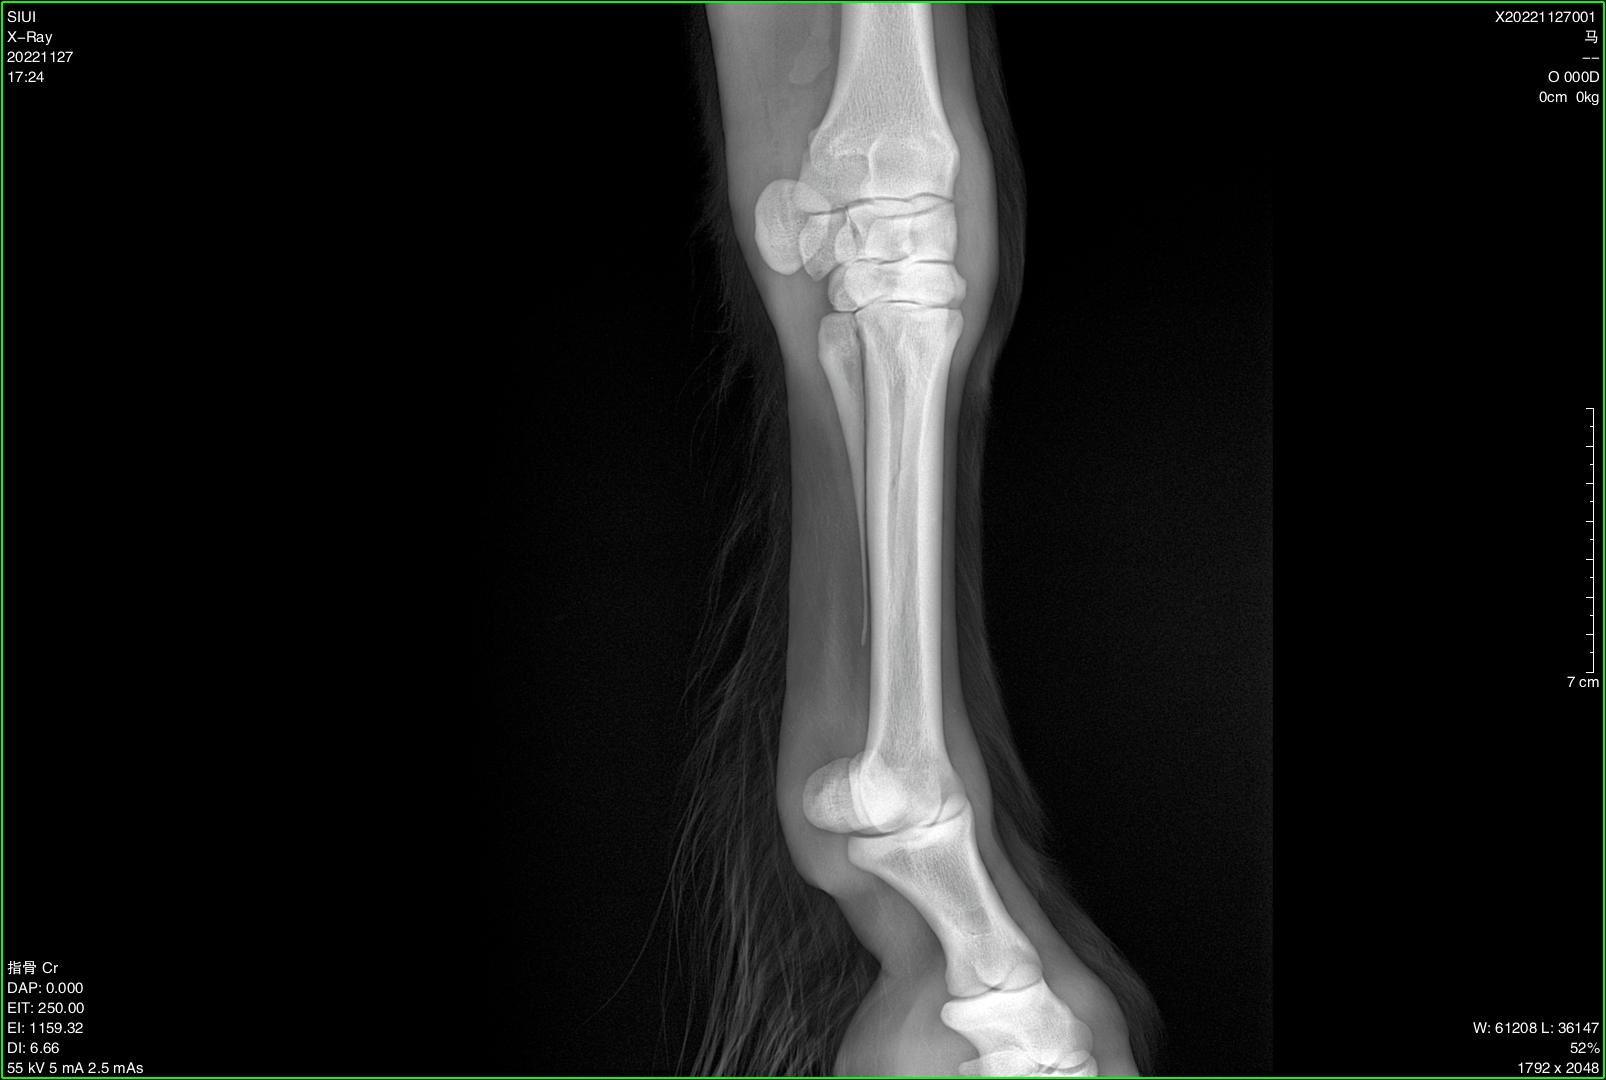

Veterinary Ultra-Portable DR System

SIUI veterinary ultra-portable DR system currently includes 2 models, SR-100 Vet and SR-300 Vet. An ultra-portable DR system consists of an ultra-lightweight X-ray generator, a wireless flat panel detector, and a user-friendly workstation.

The X-ray generators of SR-100 Vet and SR-300 Vet feature different portable designs, thereby accommodating the operational preferences of different veterinarians and adapting to diverse application environments. All-in-one backpacks, suitcases, and various types of stands are available for convenient transportation and application at stables, farms, zoos, etc.

Diverse Application Scenarios:

● Stables